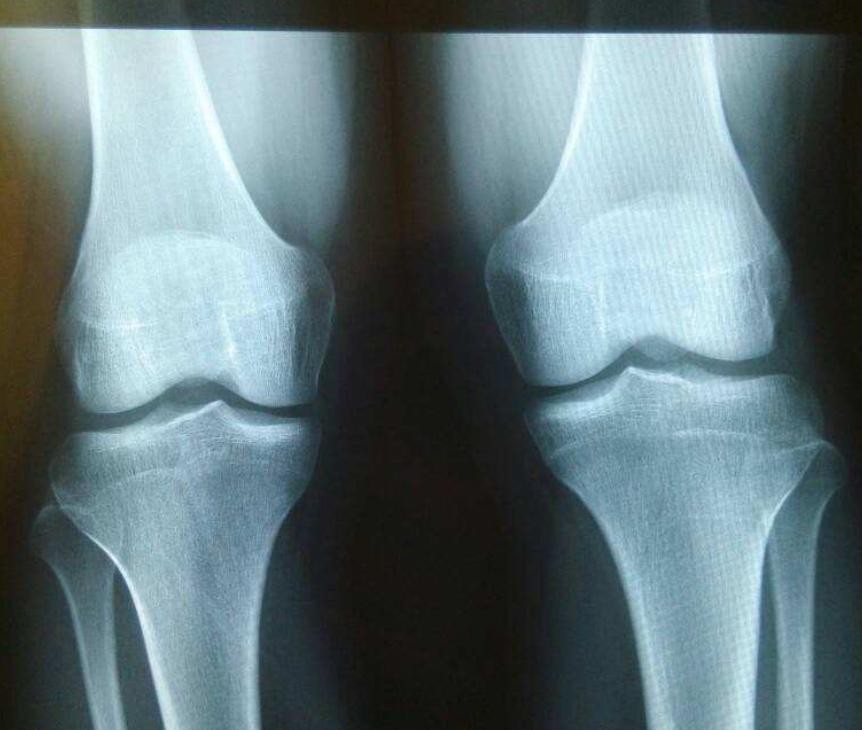

对于父母所说的以后会长高,李亚诺一开始也是深信不疑的,但是在一次医院的检查之后,医生告诉他:“你的骨垢线已经闭合了,以后基本上是不可能再通过自然发育的方式长高了。”

骨垢线

这个消息对于李亚诺来说就如同晴天霹雳额一般,他怎么也不敢相信医生所说的话,但是拍出来的CT不会骗人,李亚诺只能无可奈何地接受这个现实,最后失魂落魄的从医院里走了出来。